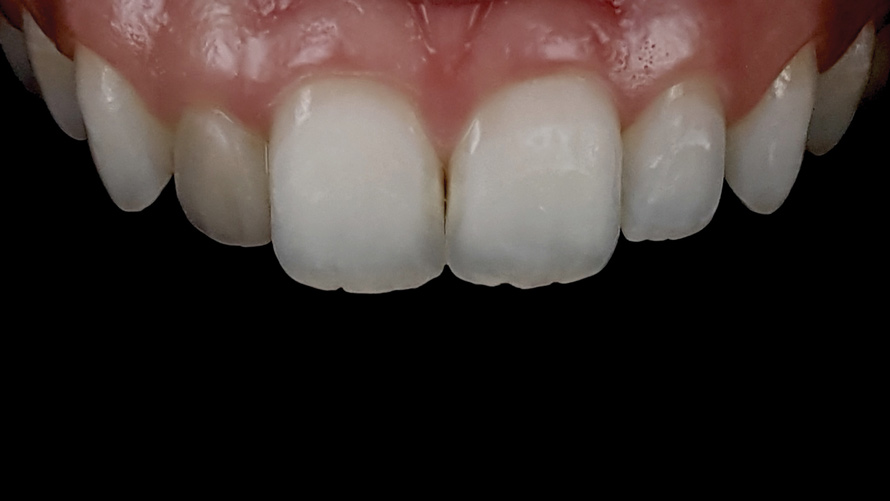

(9.) Preoperative esthetic case documentation using a smartphone and an EALS device.

Figure 9